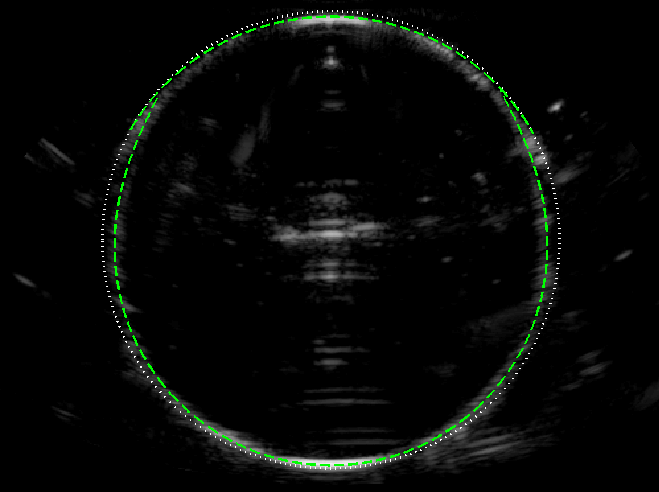

Experimental B-mode images (with curved array) of the circular test object are shown in figure 5, alongside the ray model predictions, for following 3 speed of sound scenarios.

(c) v2>v1subscript𝑣2subscript𝑣1v_{2}>v_{1}: Lastly, we take v1=1490subscript𝑣11490v_{1}=1490 m s-1 (water) and v2=1540subscript𝑣21540v_{2}=1540 m s-1 (ethanol-water mixture), giving v2/v1=1.03subscript𝑣2subscript𝑣11.03v_{2}/v_{1}=1.03. The ambient liquid is no longer matched to the scanner calibration, causing the near face to become slightly shifted towards the far face. Again, the overall image shape agrees well with the ray model (in this case in based on the extended theory in Appendix A).

These results validate the use of the ray model in predicting the geometric distortion of the object boundary.

(a)                                  (b)                                  (c)

Refer to caption Refer to caption Refer to caption

Figure 5: B-mode images of the circular object of speed v2subscript𝑣2v_{2} (imaged from above in a liquid with speed v1subscript𝑣1v_{1}), with the ray model superimposed (green dashed line). (a) v2=1490subscript𝑣21490v_{2}=1490 m s-1 and v1=1540subscript𝑣11540v_{1}=1540 m s-1, giving v2/v1=0.968subscript𝑣2subscript𝑣10.968v_{2}/v_{1}=0.968. (b) v2=1100subscript𝑣21100v_{2}=1100 m s-1 and v1=1540subscript𝑣11540v_{1}=1540 m s-1, giving v2/v1=0.71subscript𝑣2subscript𝑣10.71v_{2}/v_{1}=0.71. (c) v1=1490subscript𝑣11490v_{1}=1490 m s-1 and v2=1540subscript𝑣21540v_{2}=1540 m s-1, giving v2/v1=1.034subscript𝑣2subscript𝑣11.034v_{2}/v_{1}=1.034.